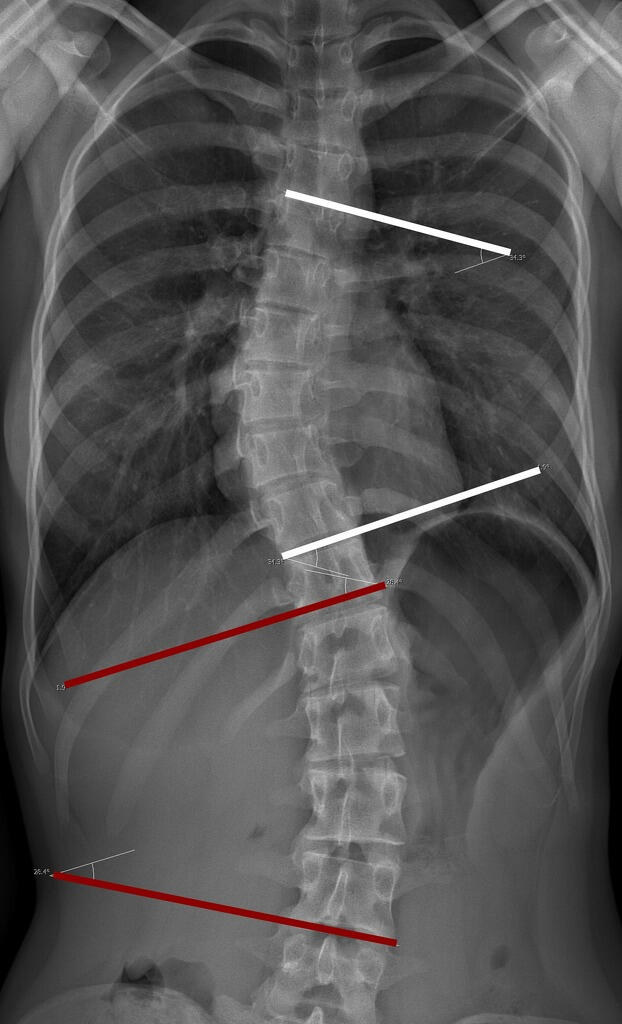

Let AI get the measurements you need and want!

- Sagittal Spine Alignment

- Horizontal / Vertical Level

- Cobb Angle